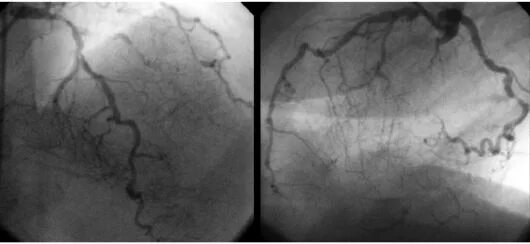

Диффузное поражение артерий